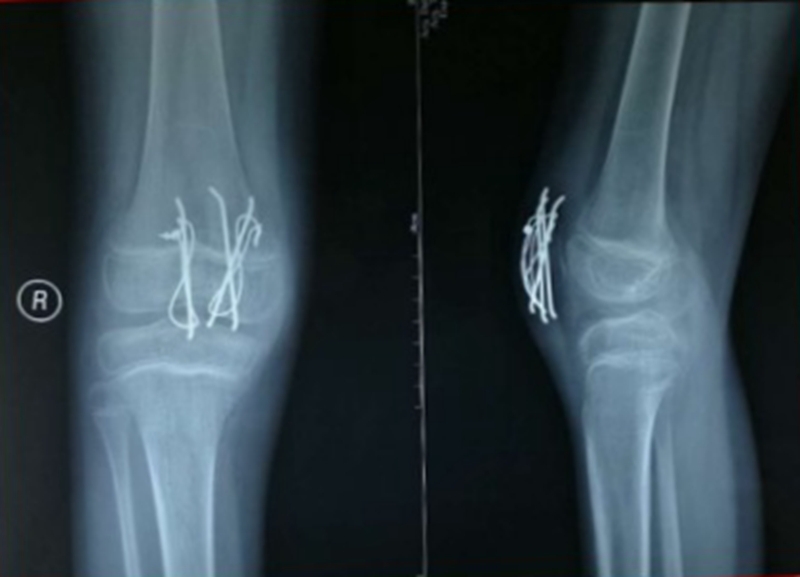

随访X线片

图9 术后8周

图10 术后3个月

图11 术后8个月

图12 术后1年